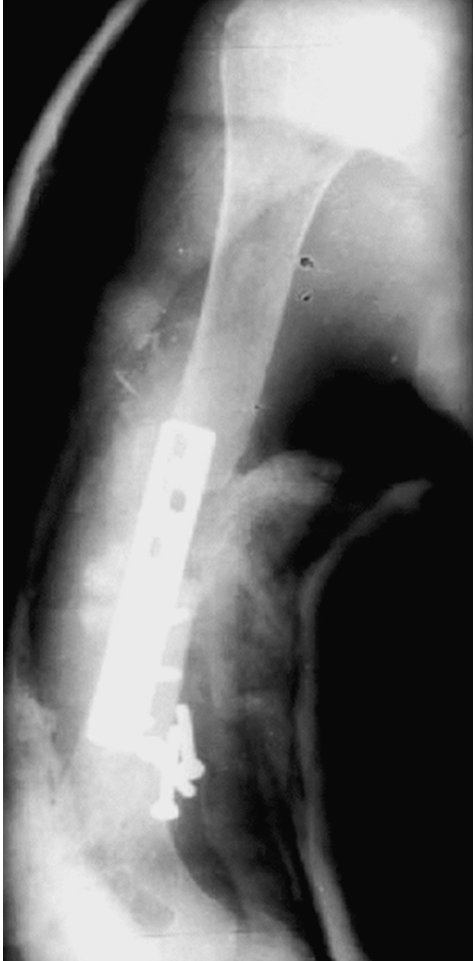

骨质疏松性骨折治疗的难点还在于骨骼质量差,严重影响内置物的固定强度。相对于正常骨,骨质疏松骨对内置入物的力学把持力较弱,术中内固定时由于骨骼脆性高容易发生爆裂骨折,骨折固定后肢体负重时易发生微骨折,或再骨折,或固定物松脱(图11-1-42)。

图11-1-42 骨质疏松性骨折内固定失效

X线片显示80岁男性肱骨干骨折患者,六孔接骨板内固定加石膏夹板外固定术后3周螺钉全部脱落